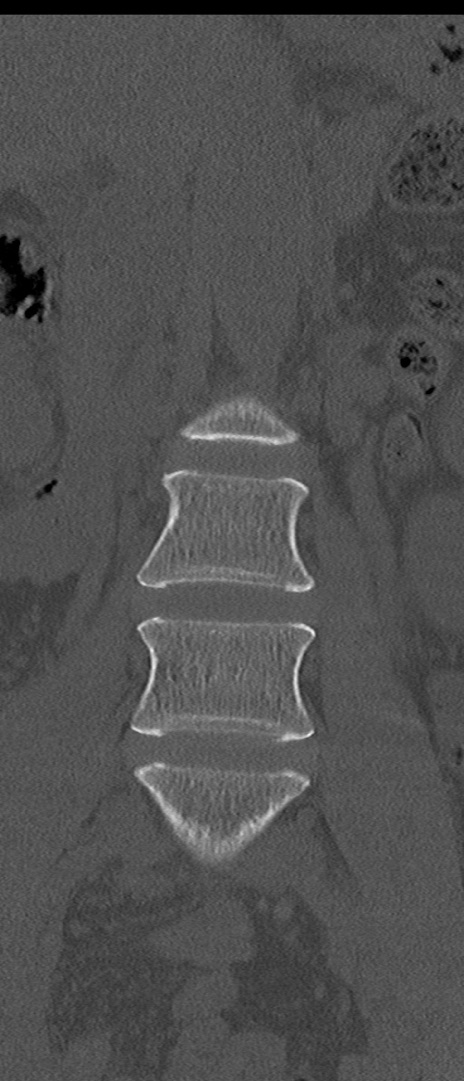

【整形】TIPS症例4 腰椎CT(冠状断像)

腰椎CT